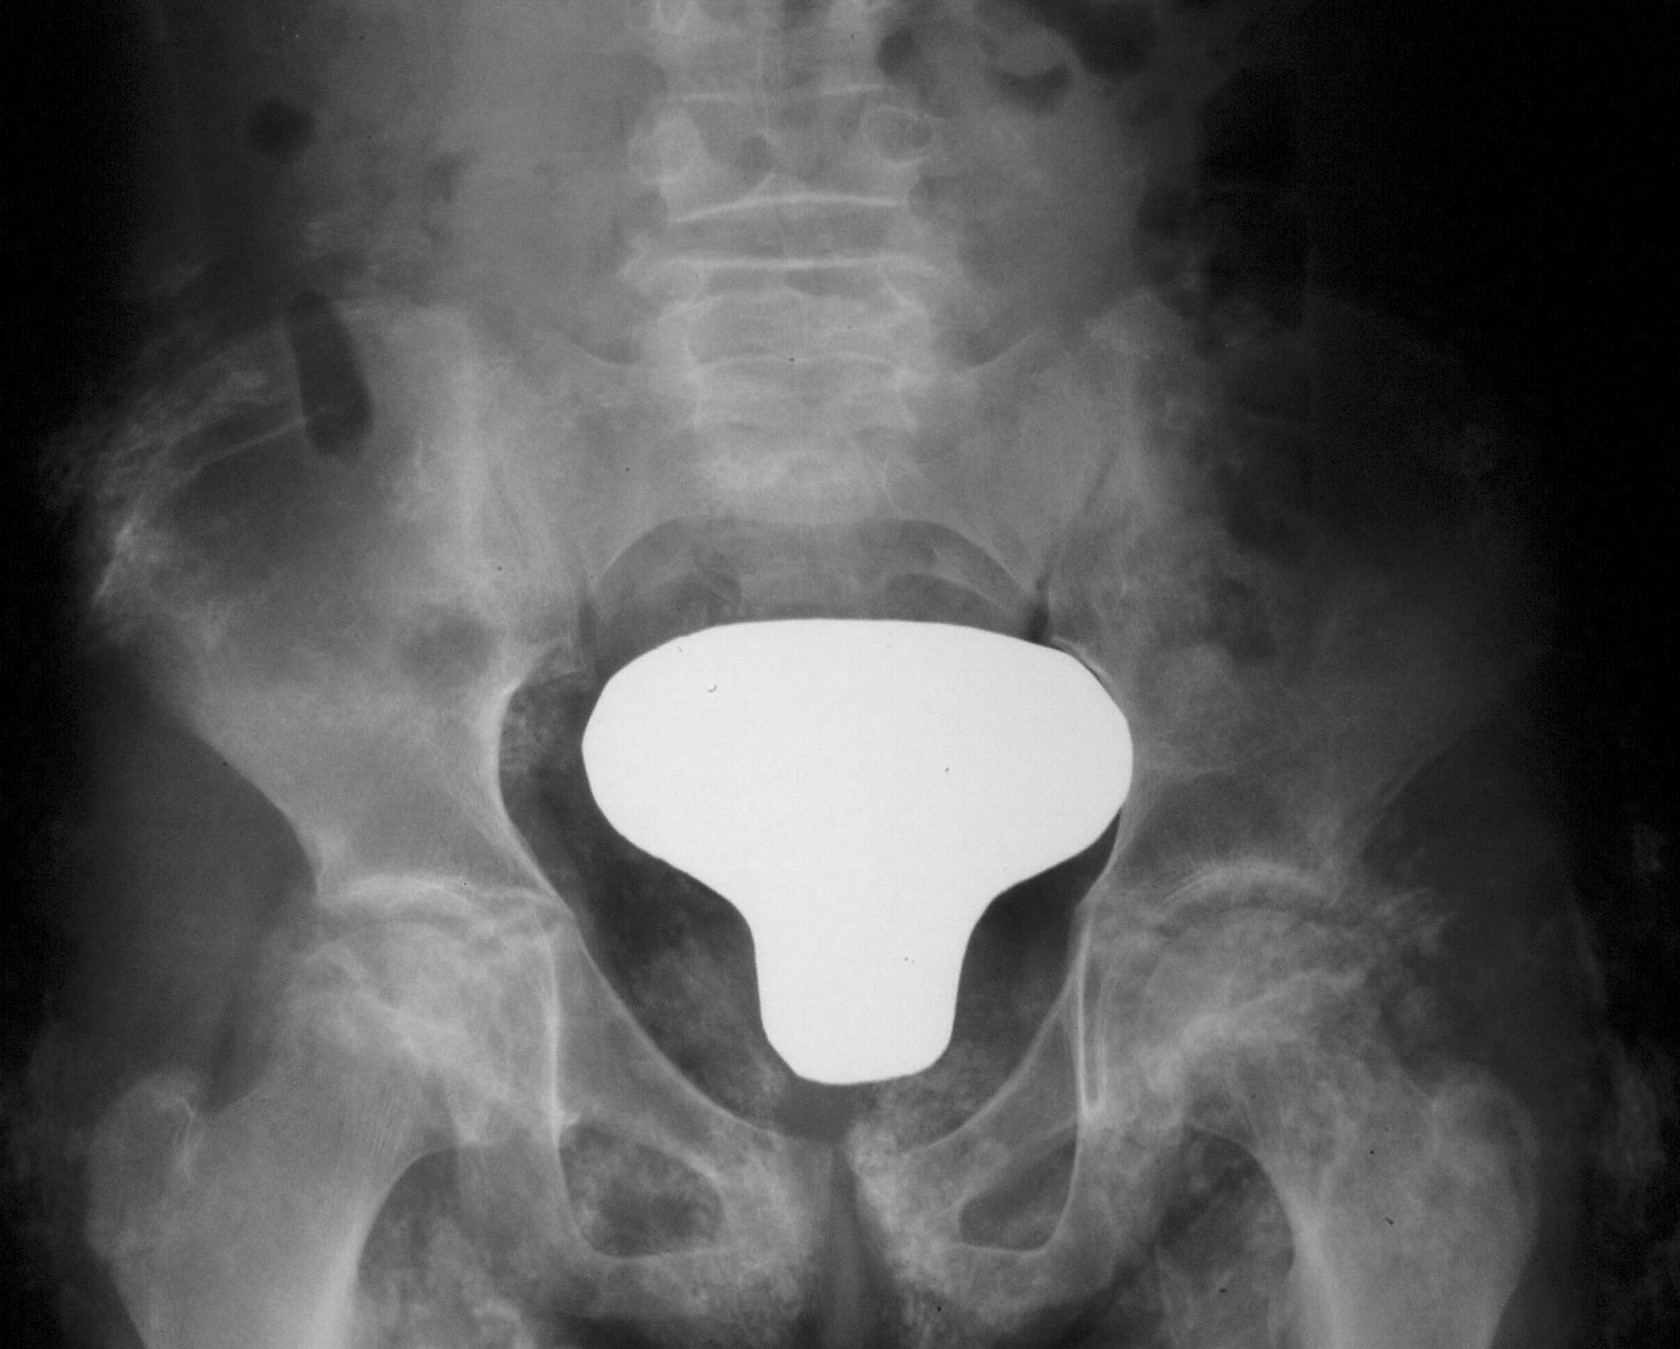

- Calcinosis (3-34%): depósito de calcio en piel, tejido celular subcutáneo y/o músculo manifestado clínicamente como lesión nodular y/o placa de consistencia dura (Figura 5). Presentes hasta en el 40% de los pacientes, frecuentemente aparecen durante la evolución, asociadas a mal control de enfermedad y/o retraso en el diagnóstico. Pueden asociar inflamación y ser dolorosas. Una de las principales complicaciones es la sobreinfección de las lesiones. En ocasiones drenan contenido líquido al exterior.